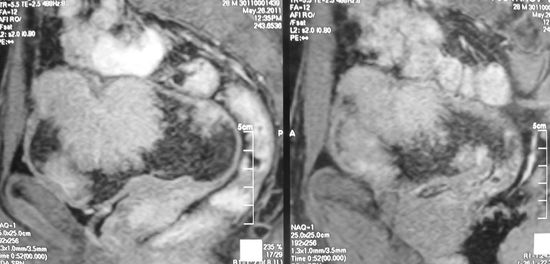

Множественные очаги переходноклеточного рака мочевого пузыря

Рецидив рака мочевого пузыря